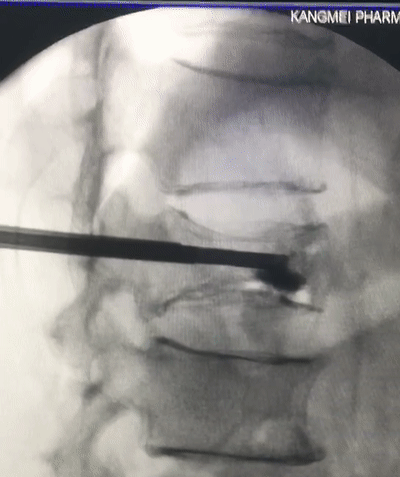

經内科綜合治療後,6月29日上午,緊張的手術正式開始。在麻醉科配合和ICU專家提供術中監護下,我院特聘專家、知名脊柱微創外科專家杜炎鑫副教授帶領團隊上台爲老人開展椎體成形術。

在我院先進的術中三維CT引導下,杜教授确定L1雙側椎弓根進針點,娴熟地将穿刺針穿入L1椎體,經穿刺針建立通道将約11ml骨水泥注入坍塌的椎體中。術中監視,注入的骨水泥逐漸支撐起原本壓縮空洞的椎體。骨水泥凝固後,病變的椎體迅速恢複了承重能力。手術持續約40分鍾,開展非常成功,術後老人的疼痛馬上消失,翻身也無疼痛,第二天就能使用助步器下地行走。